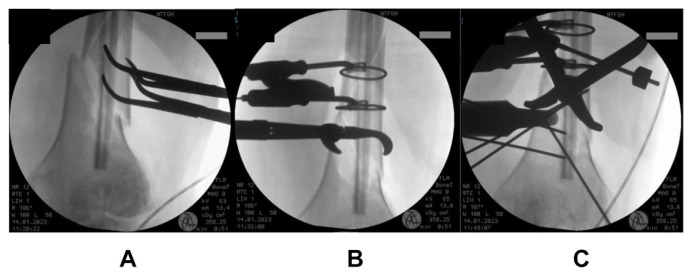

Introduction: Distal femur fractures result in high morbidity and mortality - comparable to that of hip fractures. The commonly used surgical fixation techniques today, locked plating and intramedullary nailing, have shown high postoperative complication rates. Thus, many surgeons temporarily keep patients non-weight bearing in the early postoperative stage. Increased time to ambulation after surgery is known to increase systemic complications in patients. We aim to investigate if an augmented fixation technique involving the use of a fibular strut allograft with dual locking plates helps to allow early mobilization postoperatively without adverse outcomes.

Methods: Five geriatric patients (four female, one male) with distal femur fractures (native or periprosthetic) were treated in our institution with the aforementioned technique, and were allowed early postoperative weight-bearing. These patients were followed up for postoperative outcomes. The primary outcomes studied were non union, implant failure and wound complications. Secondary outcomes studied include time to union, and Sander's functional score.

Results: There were no cases of non-union, implant failure or wound related infection. All patients achieved radiological union (mean = 12.6 weeks). Using Sander's functional scoring, two patients achieved excellent, two achieved good and one had fair outcomes. All patients were followed up for at least 6 months after operation.

Conclusion: Our method of augmented fixation with fibular strut allografts potentially allows for early weight bearing without adverse outcomes. Further studies with larger sample sizes are required to validate our findings.